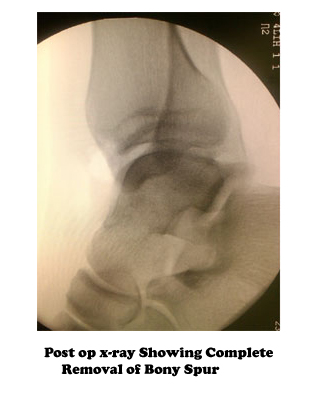

Standard ankle radiographs are necessary and are the mainstay of imaging anterior ankle impingement. The xray view of the ankle from the side (lateral radiograph) shows the ankle in profile and the bone spurs can be seen.

If non-operative treatment for anterior ankle impingement is unsuccessful, as it often is, then surgical treatment should be considered. Surgery is usually performed arthroscopically through a few very small incisions and using a video camera for assistance. The procedure is typically performed as an outpatient.